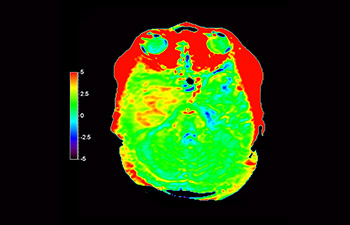

Astrocitoma cerebral, después de radioterapia

con 3D APT